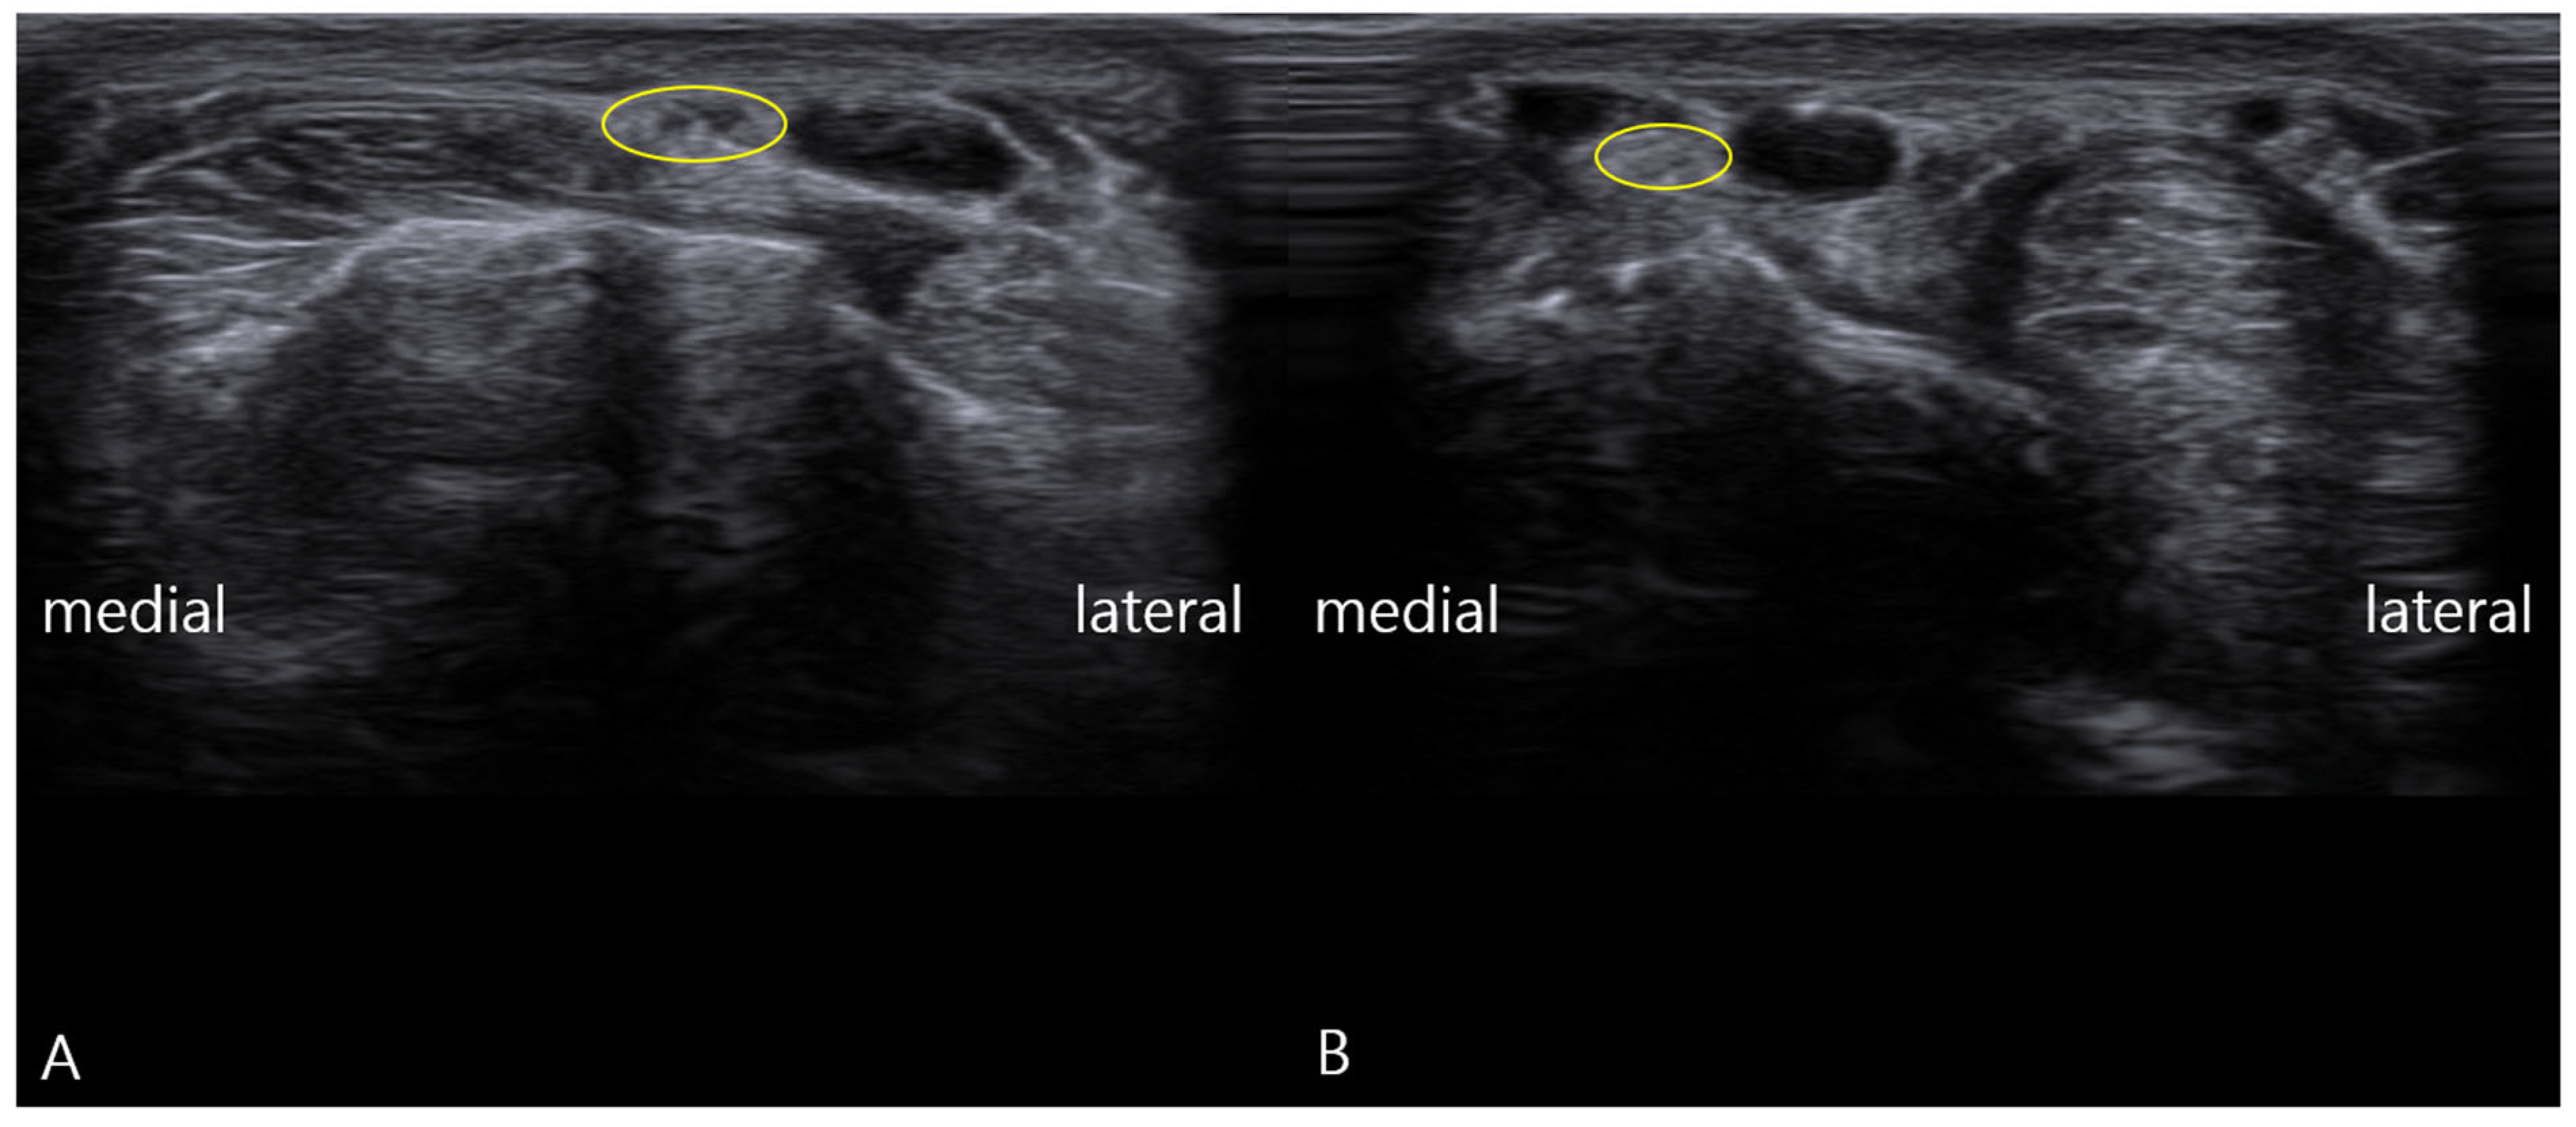

- Static Imaging: Transverse scans at the anatomical snuffbox revealed focal enlargement and loss of the normal fascicular echotexture of the SBRN on the symptomatic left side. The cross-sectional area (CSA) was measured at 0.13 cm2, significantly larger than the 0.08 cm2 on the asymptomatic right side (Figure 1). Power Doppler imaging showed mild hypervascularity around the left SBRN, suggesting ongoing inflammation.

- Ultrasonographic Evidence: Post-treatment ultrasound revealed complete normalization of the SBRN’s appearance. The CSA decreased to 0.08 cm2, matching the asymptomatic side, and the fascicular echogenicity returned to normal. Most importantly, repeat dynamic assessment showed smooth, unimpeded gliding of the SBRN over the radial styloid without any snapping.